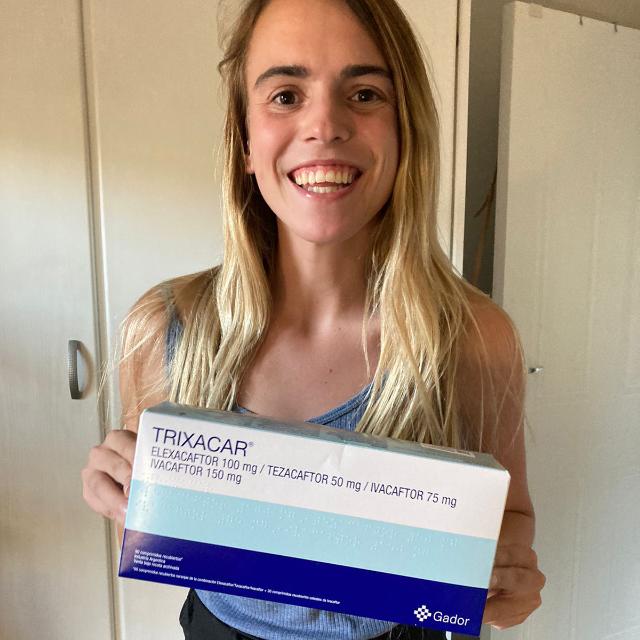

Currently, all funds donated will be going towards ensuring Lize can continue using these life-saving drugs, as it is impossible to fund alone. Trikafta is still not registered in South Africa, and using Trixacar as a South African patient costs more than R70,000 per month. We hope to raise enough money to give to other patients as well.

Help Lize to continue using this medication and ensure a quality of life that was never before promised. We believe in transparency and will deliver regular updates in the Blog section.

Join me on this journey as I navigate the challenges and triumphs of living with cystic fibrosis, and explore the potential of this new medication. Together, let's push some boundaries and redefine limits!